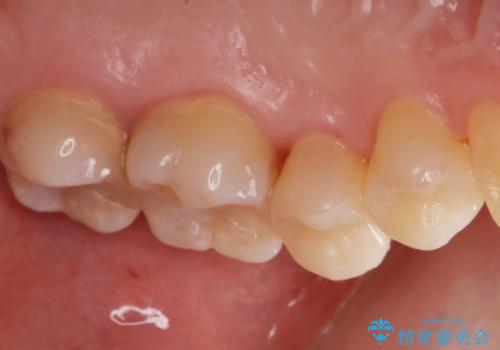

適合の良い詰め物が入りました。

虫歯がある状態で矯正を行うと矯正中に虫歯が悪化する可能性があるので先に治療を行なってから矯正をはじめます。

他の部位も治療予定です。